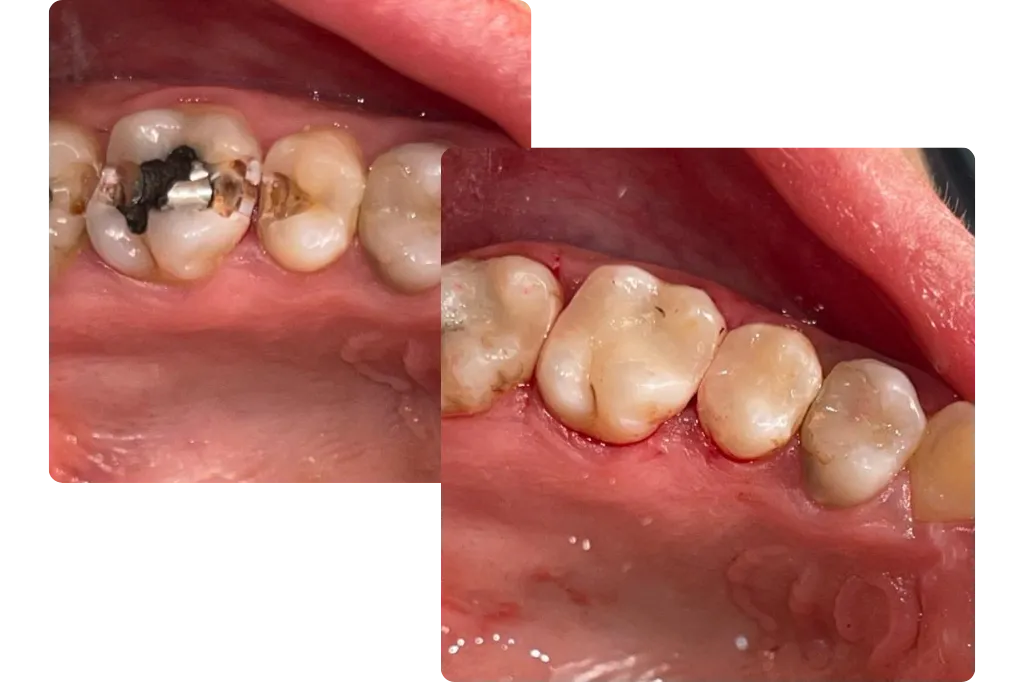

To understand why dental fillings are needed, you should understand what a cavity is and what it can do to a tooth. A cavity is a hole in the enamel of a tooth created by dental decay. You may not realize you have a cavity until the hole exposes the tooth’s nerve, which can cause pain when consuming hot or cold foods or drinks.

Cavities can also cause teeth to ache, which signals that you should go to a dentist. Upon discovering the cavity, one of our dentists will remove the decay, which often means enlarging the hole in the enamel. Then, they will fill the hole to keep the decay from returning and restore your ability to use the tooth to chew and speak.

Our dentists at U Smile Family Dentistry give their patients in Mesa, AZ, several options for materials when filling cavities. However, if you are concerned about people seeing the dental work you have, then selecting composite fillings will not only protect your tooth, but many people will never see your fillings.The composite material that goes in the tooth is a combination of ceramic and plastic that produces a strong substance. The composite allows a tooth to bear up to 95 percent of the weight a natural tooth does, and it restores the patient’s ability to eat the foods they love. More people are choosing composite fillings because they blend in with natural teeth so well.Our dentists at U Smile Family Dentistry can match the composite color to the shade of your teeth. Not all teeth are perfectly white, so our dentists in Mesa, AZ, can add the tints necessary to match your teeth. If you’re interested in getting composite fillings, contact our offices for an appointment.